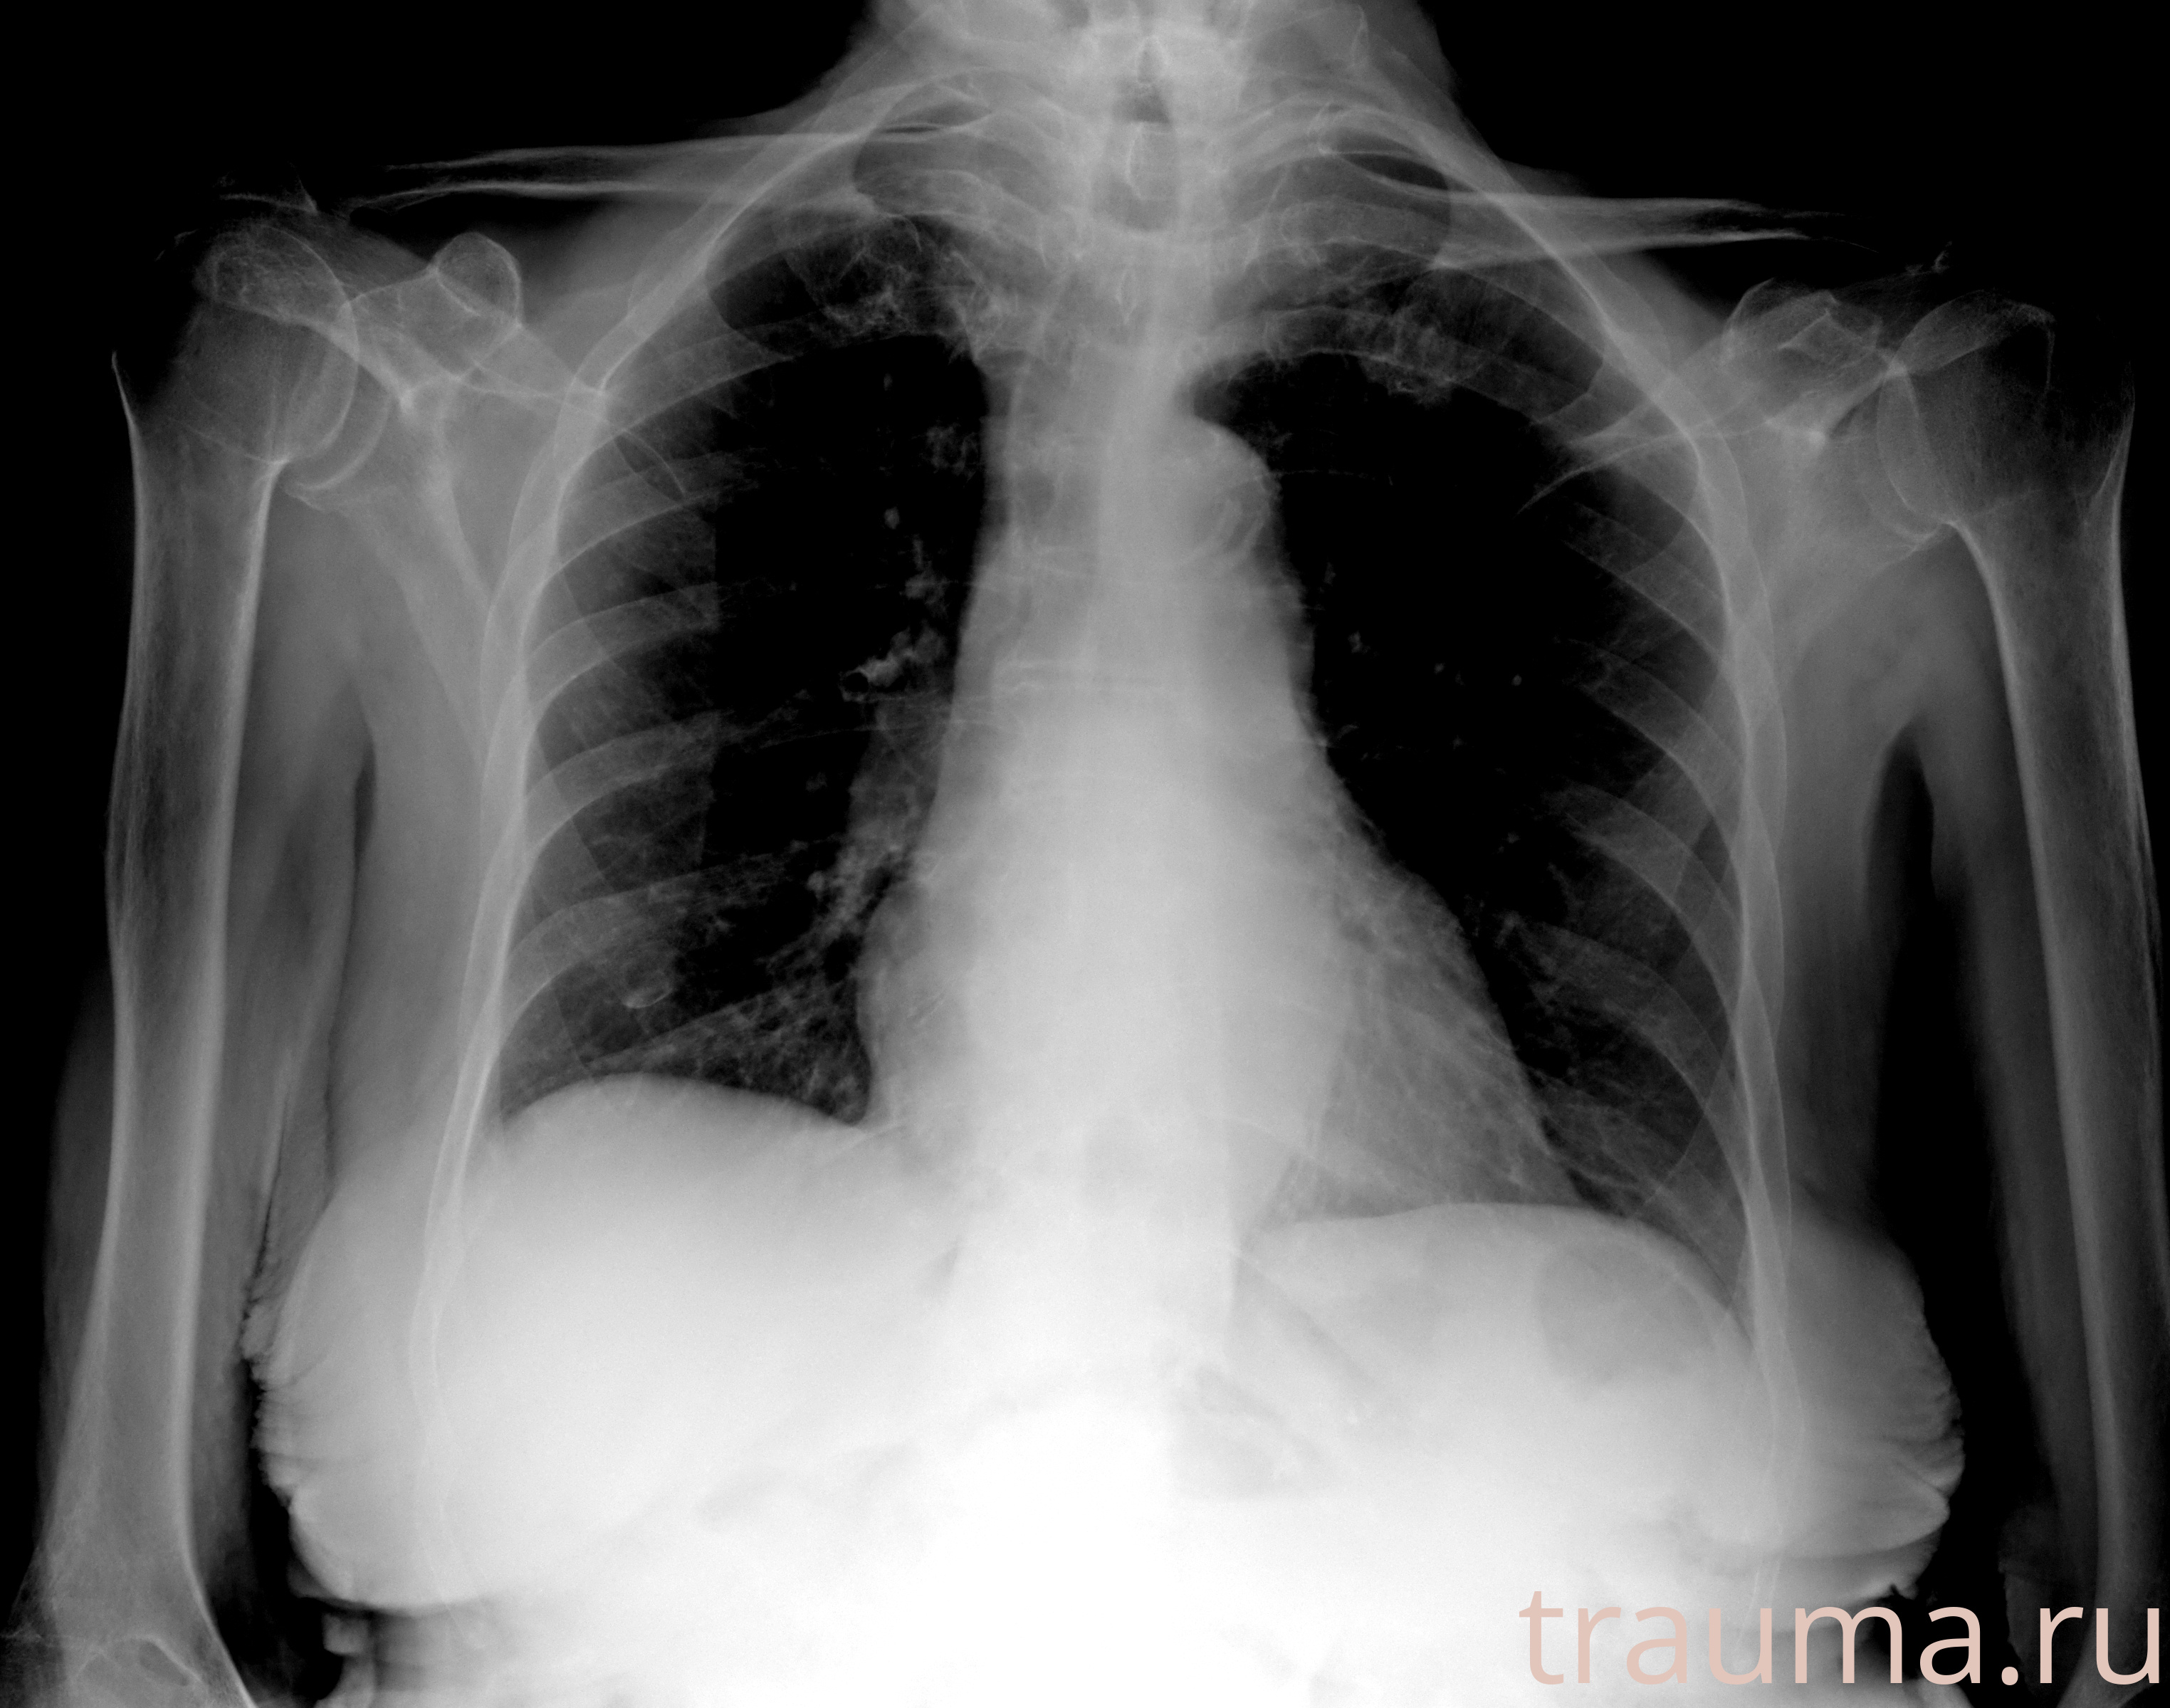

Рентген на дому: по вашему адресу приезжает врач-рентгенолог, травматолог-ортопед с мобильным рентгеновским аппаратом, проводит диагностику травмы или заболевания, делает необходимые рентгенограммы, дает рекомендации по дальнейшему лечению. Получить качественные снимки в домашних условиях возможно благодаря уникальной методике, разработанной МосРентген Центром для института  Склифосовского